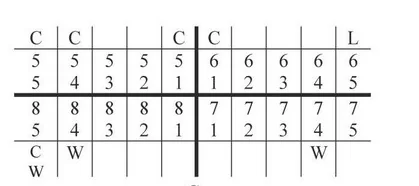

Instrumentem przedstawionym na ilustracji stosowanym w chirurgii stomatologicznej jest

| 1 | 1 | 1 |

| 17-14 | 13-23 | 24-27 |

| 47-44 | 43-33 | 34-37 |

| 1 | 3 | 1 |